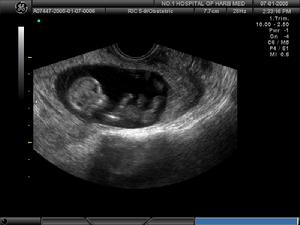

超聲成像超聲成像是利用超聲的物理特性和人體器官組織聲學性質上的差異,以波形、曲線或圖像的形式顯示和記錄,藉以進行疾病診斷的檢查方法。40年代初就已探索利用超聲檢查人體,50年代已研究、使用超聲使器官構成超聲層面圖像,70年代初又發展了實時超聲技術,可觀察心臟及胎兒活動。超聲診斷由於設備不似CT或MRI設備那樣昂貴,可獲得器官的任意斷面圖像,還可觀察運動器官的活動情況,成像快,診斷及時,無痛苦與危險,屬於非損傷性檢查,因之,在臨床上套用已普及,是醫學影像學中的重要組成部分。不足之處在於圖像的對比分辨力和空間分辨力不如CT和MRI高。

人體結構對超聲而言是一個複雜的介質,各種器官與組織,包括病理組織有它特定的聲阻抗(表1-4-1)和衰減特性。因而構成聲阻抗上的差別和衰減上的差異。超聲射入體內,由表面到深部,將經過不同聲阻抗和不同衰減特性的器官與組織,從而產生不同的反射與衰減。這種不同的反射與衰減是構成超聲圖像的基礎。將接收到的回聲,根據回聲強弱,用明暗不同的光點依次顯示在影屏上,則可顯出人體的斷面超聲圖像,稱這為聲像圖(sonogram或echogram)。

人體器官表面有被膜包繞,被膜同其下方組織的聲阻抗差大,形成良好界面反射,聲象圖上出現完整而清晰的周邊回聲,從而顯出器官的輪廓。根據周邊回聲能判斷器官的形狀與大小。 超聲經過不同正常器官或病變的內部,其內部回聲可以是無回聲、低回聲或不同程度的強回聲